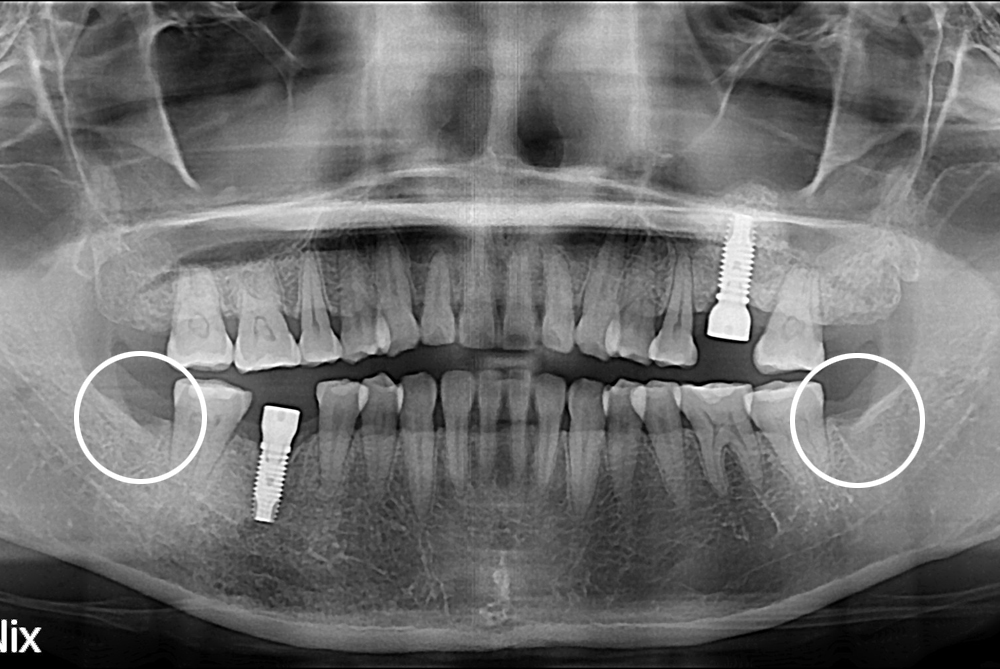

[사랑니] 난발치 사랑니 발치

치료전 : 2017-05-17